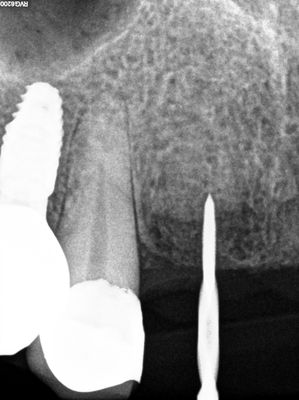

relatively straight forward implant placement in the upper anteriors, densah drills used after 2.2mm twist drill. 21 loss of stablity, spinning, when trying to place deeper, removed implant, deepened osteotomy, implant replaced with good stability.